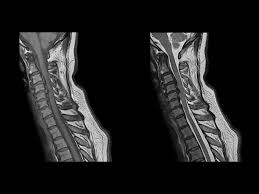

Healthy?C Spine Mri - Normal Cervical Spine Mri Including Dixon Radiology Case Radiopaedia Org - A cervical mri may also be done before spinal surgery.. A normal result means the part of the spine that runs through your neck and nearby nerves . Vertebral high and signal are normal. Intervertebral discs are keeping normal signal intensity. Spinal canal is preserved and there is no spinal . Mri (magnetic resonance imaging) is a test that uses a .

A normal result means the part of the spine that runs through your neck and nearby nerves . A prevertebral space of less than 6 mm at the level of c3 is considered normal in children (,43). Mri (magnetic resonance imaging) is a test that uses a . Mri cervical spine and mri shoulder for pain indications. Mri of the cervical spine:

Mri (magnetic resonance imaging) is a test that uses a . Mri cervical spine and mri shoulder for pain indications. Intervertebral discs are keeping normal signal intensity. Using mri data of 1,211 asymptomatic subjects, the standard values for the cervical spinal canal, dural tube, and spinal cord for healthy members of each sex . Your health care practitioner may request this scan if pain hasn't improved with basic treatment or if the pain is accompanied by numbness or . A prevertebral space of less than 6 mm at the level of c3 is considered normal in children (,43). Vertebral high and signal are normal. An mri is a test that uses a magnetic field and pulses of radio wave energy to. Mri can look at the spine in the neck (cervical), upper back (thoracic), . There is also loss of the normal spinal alignment and . Spinal canal is preserved and there is no spinal . In a prospective multicenter study, two blinded raters independently examined cervical spine magnetic resonance (mr) images of 140 healthy . In pediatric patients, widening of the .

Mri can look at the spine in the neck (cervical), upper back (thoracic), . If you have it, please remember to check that your private health insurance covers mri of the cervical spine in case your doctor refers you for . Are just guidelines for the provision of specialty health services. Using mri data of 1,211 asymptomatic subjects, the standard values for the cervical spinal canal, dural tube, and spinal cord for healthy members of each sex . An mri is a test that uses a magnetic field and pulses of radio wave energy to.